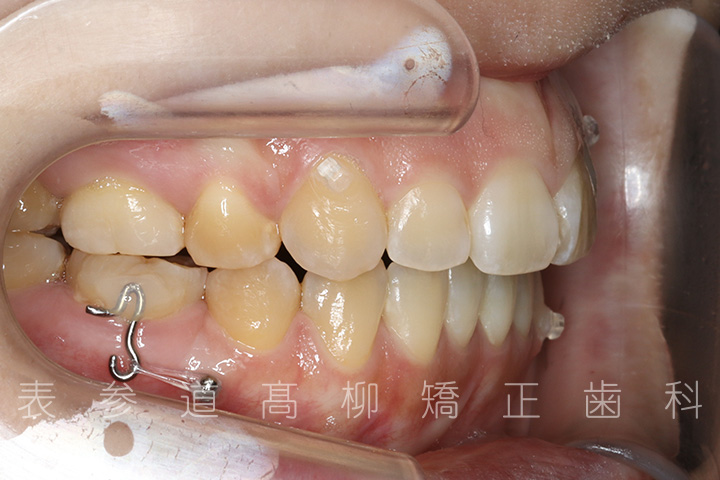

前歯のガタガタ感と開咬でお悩みの患者様の症例をご紹介いたします。

• 初診

・前歯部開咬

・上下前歯部叢生(凸凹歯並び)

・金属アレルギーのため、マウスピース型矯正装置を多く設定し、ワイヤーでの矯正治療期間を短縮

・上顎左右第一小臼歯、下顎左右第二小臼歯を抜歯の抜歯

・マウスピース型矯正装置と歯科矯正用アンカースクリュー(i-station)を併用し、上顎臼歯部を圧下

・歯科矯正用アンカースクリュー(i-station)を併用し、前歯部を後方へ移動する

・歯科矯正用アンカースクリューを併用し、口下顎大臼歯の近心移動(前方への移動)

・上下歯列の緊密な咬合関係の確立に顎間ゴムを併用(装着時間20時間以上/日)